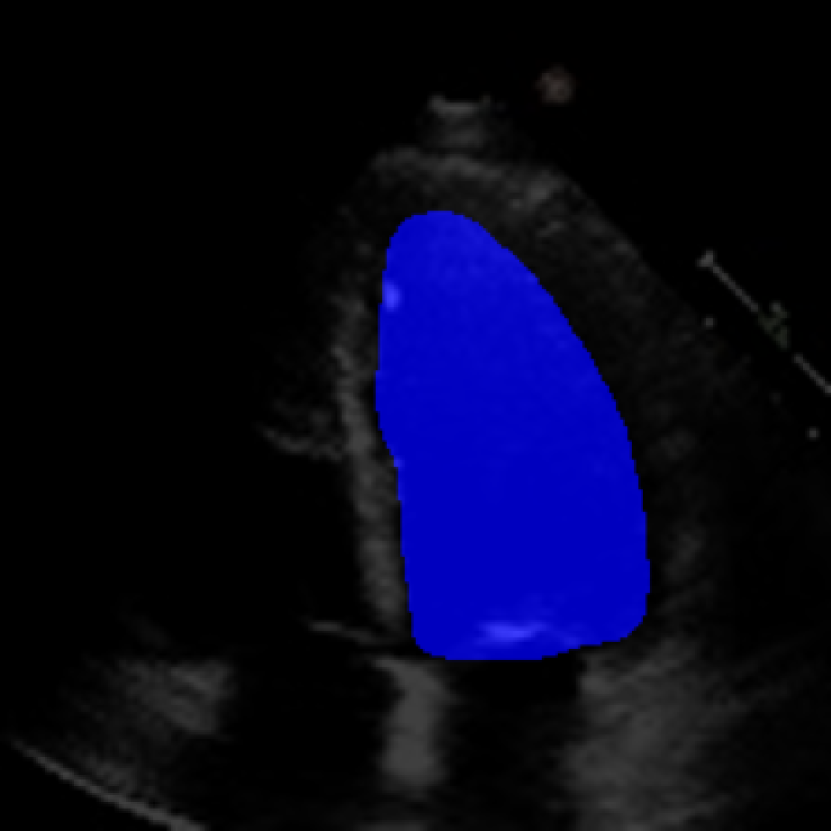

The 112x112 input is first resized to 299x299 as required by the Xception model. The Beat Extractor is then used to feed only whole beats to the LVEF estimation pipeline. A modified DeepLabV3+ model segments the left ventricle for every frame of the echocardiogram video (Figure LABEL:fig:segmentation). The area is measured, and a peak detector is then used to find the maximum (diastole) and minimum area (systole). The frame numbers corresponding to these extrema are recorded, and the video is clipped into smaller videos that go from diastole to systole. These smaller videos are independently fed to the Xception based feature extractor.

The ConFormer model demonstrated high performance in the estimation of Left Ventricular Ejection Fraction (LVEF) from echocardiogram videos (Figure 2). The model achieved a mean absolute error of 6.57 in LVEF prediction, indicating a high level of accuracy in its estimations (Table I). Notably, ConFormer outperforms the full video assessment of LVEF by EchoNet-Dynamic, a significant achievement given the model’s efficiency. With just 5.82 million parameters, ConFormer is significantly more efficient than existing models, making it a practical tool for real-world applications.